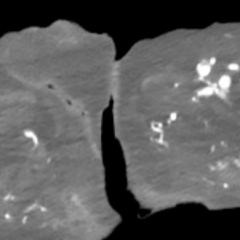

This case report discusses a 36-year-old male who presented to the emergency department with an atypical story for acute coronary syndrome (ACS). Initially, the patient was felt to have a non-diagnostic electrocardiogram (ECG). Once the laboratory test results were obtained and the initial high-sensitivity troponin was noted to be elevated, the initial ECG was again reviewed. The patient was felt this time to have an abnormal ECG, demonstrating borderline ST elevation in leads I, aVL, and V2-V5. The interventional cardiologist on call was contacted, and the cardiac catheterization lab was activated. Upon left heart catheterization, the patient was found to have a spontaneous coronary artery dissection (SCAD) of the distal left anterior descending (LAD) artery. Post-catheterization, the patient was observed on cardiac telemetry and started on dual antiplatelet therapy. Echocardiogram revealed a preserved ejection fraction (EF), but hypokinesis of the apical anterior, anterolateral, inferior, and apical myocardium. The patient was discharged within 48 hours without any complications.